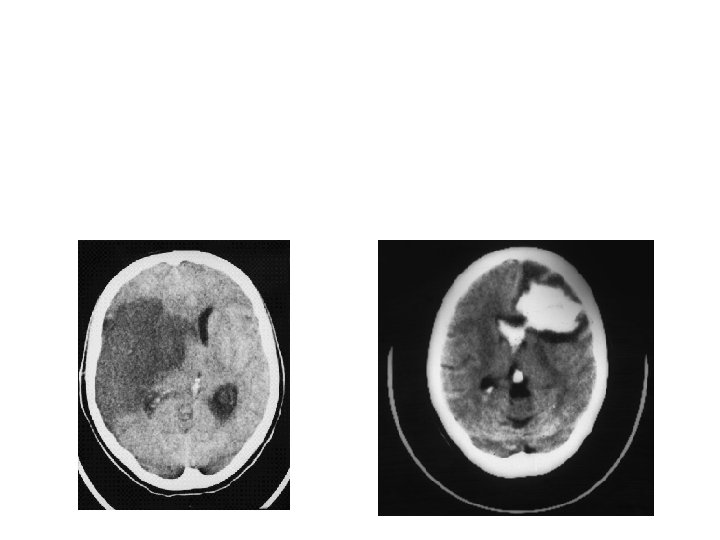

Ischemia with Bleeding 10 -15%